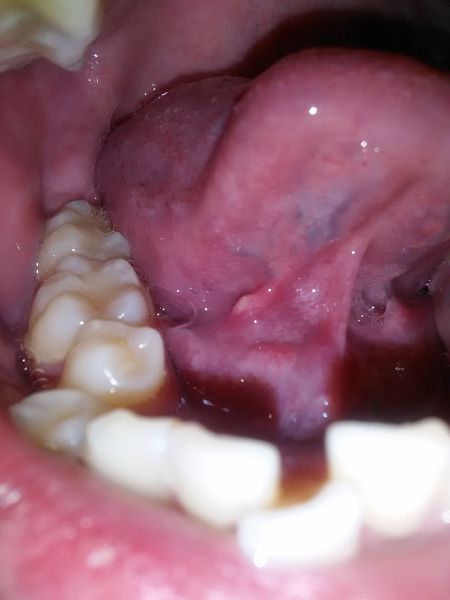

舌头底下溃疡图片

之前舌头下面外侧在吃饭时感到扯痛,过后张了个肉芽上面有溃疡.2.

舌头下长出一块肉,上面好多溃疡,很痛.